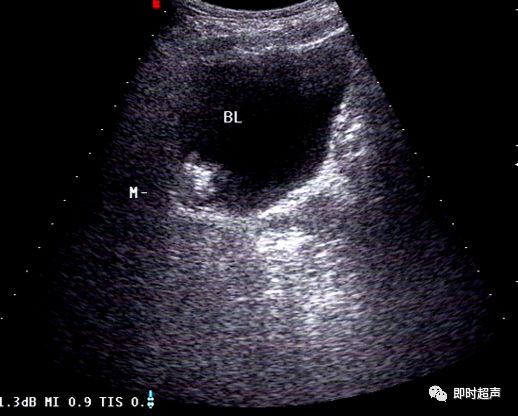

超声表现:

- 膀胱异物表现为液性暗区中可见杆状、细棒状等形态多样的回声水平不一的回声,内无血流信号显示,随体位移动,膀胱壁光滑,连续良好

- 膀胱凝血块表现为液性暗区内可见絮状、团块状的中、低回声,随体位移动,团块内部及周边均无血流信号

各种形态的膀胱凝血块(箭头)